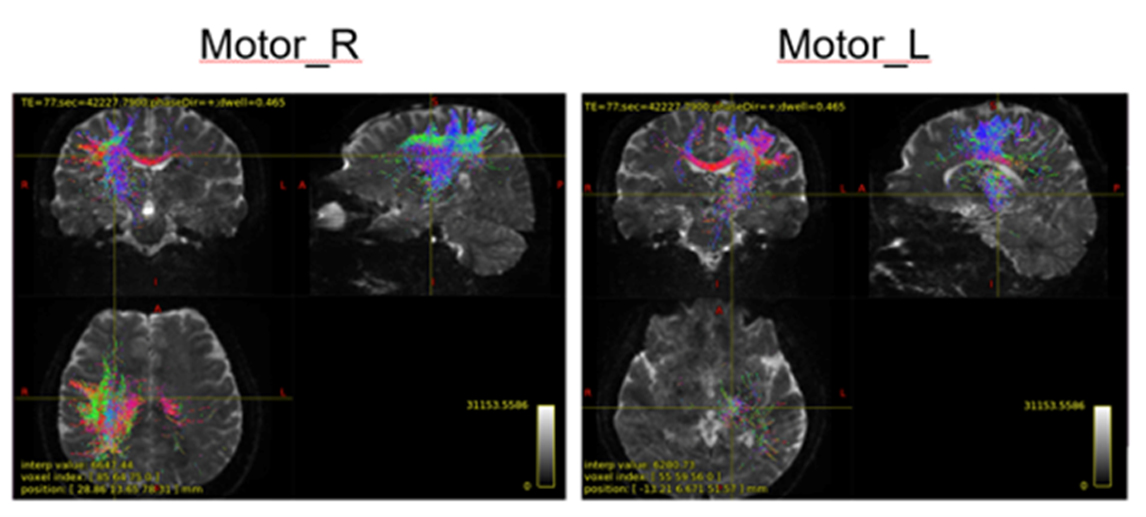

近年MRI的技术获得了长足的发展,现已实现了神经纤维束的追踪成像。下图为通过弥散张量成像(DTI)手法,描述的脑神经信号详细结构图。

上图为运动区左右横断面成像,可以通过这种方式观察大脑的活跃部位。